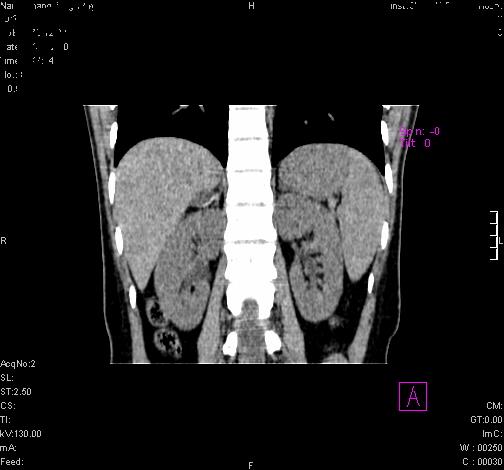

患者为年轻女性,查体发现右侧肾上腺囊性占位。无临床体征。

这么漂亮的图像,一看一目了然。典型的右侧肾上腺囊肿,周围有钙化。感谢搂主!

“肾上腺囊肿组织学分为4类:1)内皮细胞性,2)假性囊肿,3)寄生虫性,4)上皮细胞性。其中内皮细胞性最为常见。假性囊肿多为肾上腺内出血后遗留囊腔,囊壁无上皮细胞。寄生虫性多为包虫病引起。上皮性则很少见。”

这么明显的弧形钙化,多考虑包虫病所致的寄生虫性囊肿。

右侧肾上腺囊性密度灶囊壁有钙化。考虑肾上腺囊肿,结核?

右侧肾上腺囊肿,周围有钙化。